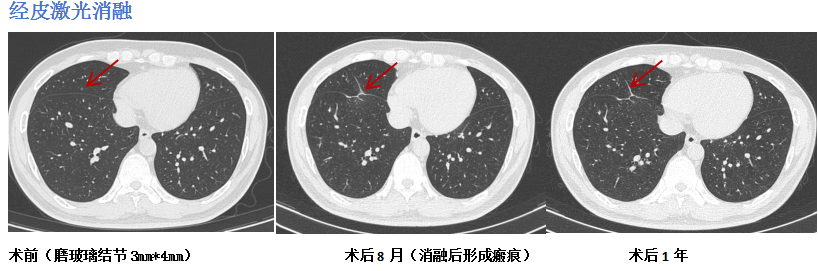

面对不同的结节特性,团队拥有一个丰富的“消融技术武器库”,包括射频消融、微波消融、激光消融、冷消融(氩氦刀)及热蒸汽消融等。